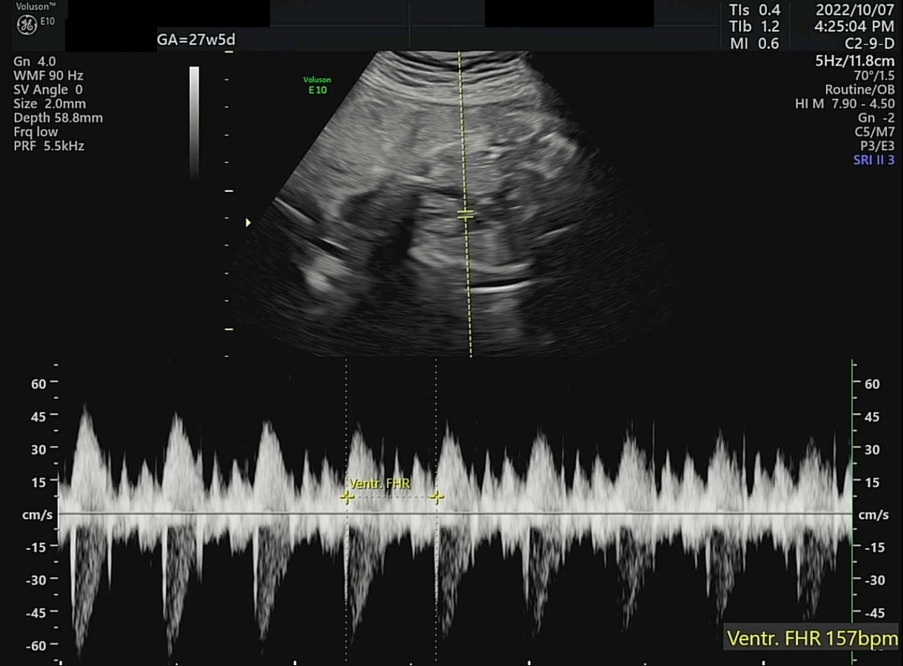

오늘은 병원에서 4D 입체 초음파를 찍기로 예약한 날이다. 입체 초음파는 아기의 모습을 입체적으로 사진 찍듯이 볼 수 있는데, 27주쯤에 찍어야 아기도 통통하게 살이 올라 예쁘게 찍힌다고 하여 이때 예약했다. 초음파실에 들어가서 아기가 주수에 맞게 잘 컸는지부터 확인했다. 2주 전 860g 정도였던 써니는 벌써 1kg를 돌파하여 1096g이 되었다. 임신 28주 이후에 체중이 1000g을 넘은 아기는 조산하여도 NICU(Neonatal Intensive Care Unit, 신생아 집중치료실)에서 치료를 받을 경우 생존 가능성이 95% 이상이다. 가장 친한 친구 중 한 명이 NICU 간호사인데, 매번 써니의 체중을 물어보았었다(직업병..?). 이제 1kg를 넘었으니 혹시나 세상에 일찍 나와도 이모한테 가면 살 수 있다. 그래도 이모 일터에는 가지 말자 써니야...

왼쪽부터 심박수, 양수량 확인, 머리 좌우 직경과 둘레 그리고 그에 따른 예상 분만일. ± 1주정도는 일반적이다.